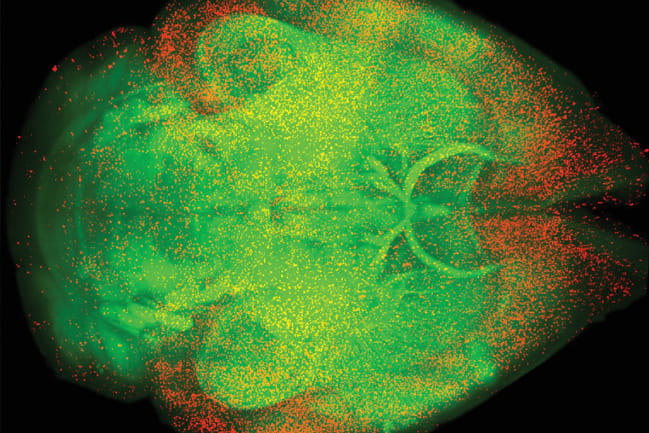

Unbiased whole-brain mapping of c-Fos identifies active brain regions following a rewarding dose of oxycodone. c-Fos-positive cells are shown in red; white matter tracks are shown in green. Credit: Alexander Smith.

In a study published in the June 7 issue of Science, Smith and his team found that an understudied brain region responsible for aversion, the dorsal peduncular nucleus, is highly responsive to opioids. Surprisingly, the opioid receptors in this brain region respond uniquely to opioids, contradicting the prevailing belief that opioids act primarily through dopamine in the brain. This discovery offers an exciting new area of research.

The team, led by Smith and his mentor Paul Kenny, found that mu opioid receptors are abundant on cells in the dorsal peduncular nucleus. The opioid receptors in this region do not result in disinhibition; rather, they are found directly on cells that project to a part of the brain that drives aversive feelings. When opioids bind to these cells, they inhibit them. Removing these aversive feelings leads to reward – a process called negative reinforcement. This contributes to the pleasurable and addictive qualities of opioids.